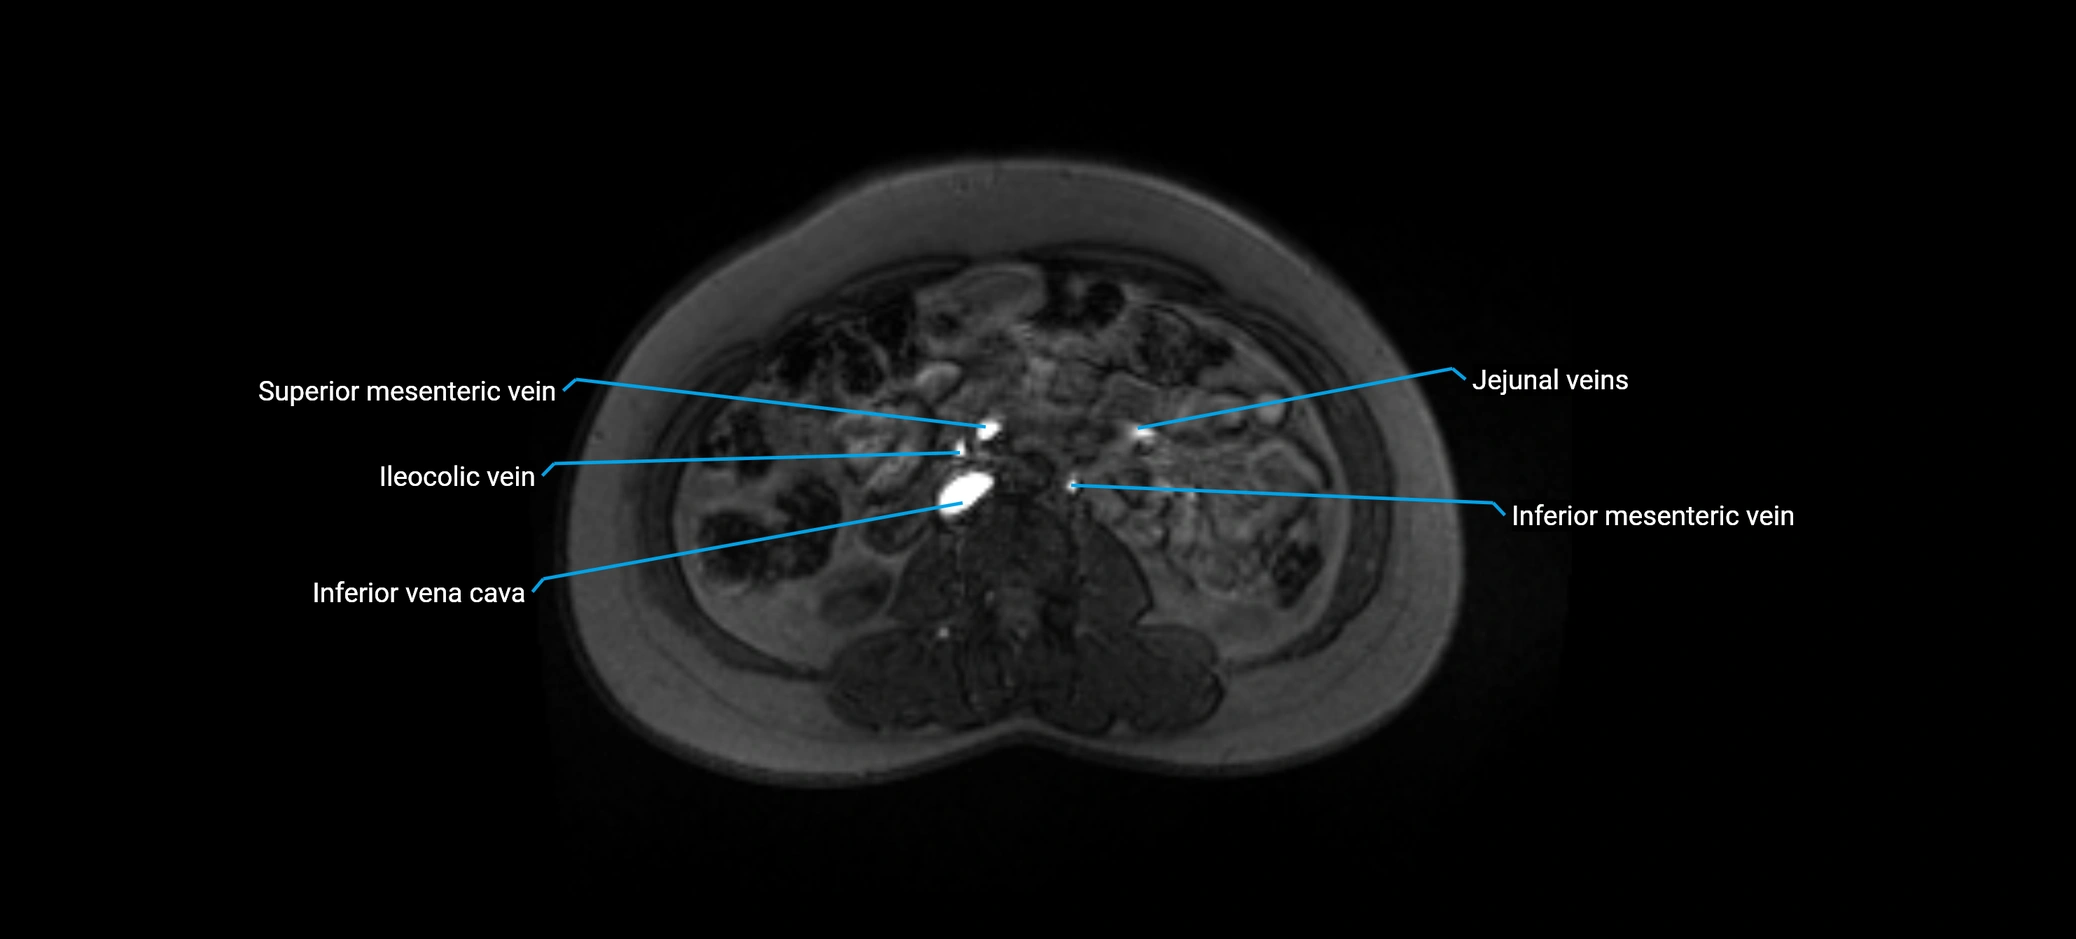

MRI image

image